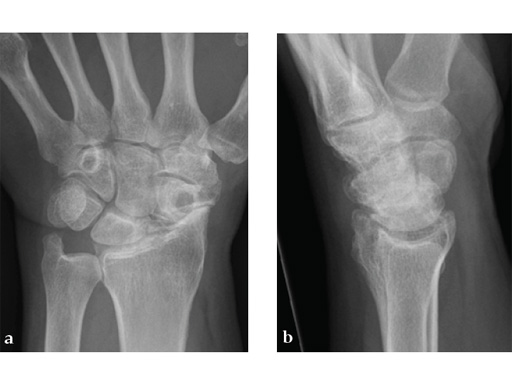

Fig 1ab Preoperative x-rays. Note the carpal collapse a a b nd DISI deformity.